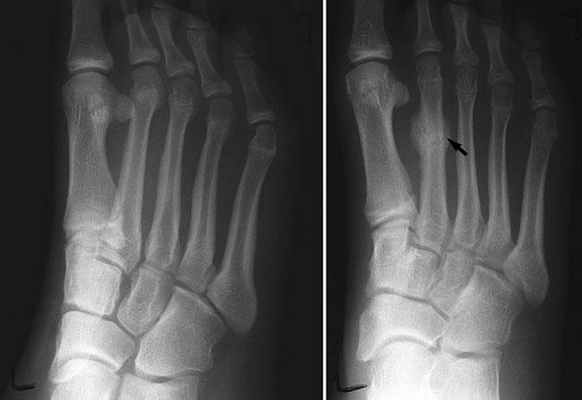

«Золотой стандарт» для диагностики стресс-переломов — это магнитно-резонансная томография (МРТ). А вот рентгенограммы не позволяют диагностировать острые стрессовые переломы, так как разрешающей способности метода не достаточно, чтобы определить микротрещины. Поэтому делать рентген имеет смысл только через 2–3 недели после усталостного перелома, когда в месте перелома уже образуется костный мозоль, видимый при рентгеновском облучении.

На приёме у доктора вам назначат обследование. Вероятно, это будет сканирование при помощи компьютерной томографии или магнито-резонансной томографии, поскольку рентген не может выявить перелом на ранней стадии.

Если после первичной оценки есть подозрения на стрессовый перелом, терапевту следует направлять пациента на диагностику для подтверждения или опровержения диагноза. Рентгеновские снимки обычно используются для диагностики стрессовых переломов, несмотря на плохую чувствительность. Стрессовые переломы обычно не проявляются на рентгенограмме в течение 2 – 6 недель после травмы; когда они становятся видимыми, появляются в виде полос просветления и могут иметь кортикальное уплотнение. Остеосцинтиграфия является наилучшей диагностической визуализацией стрессовых переломов (переломы заметны во 2-3 день после травмы).